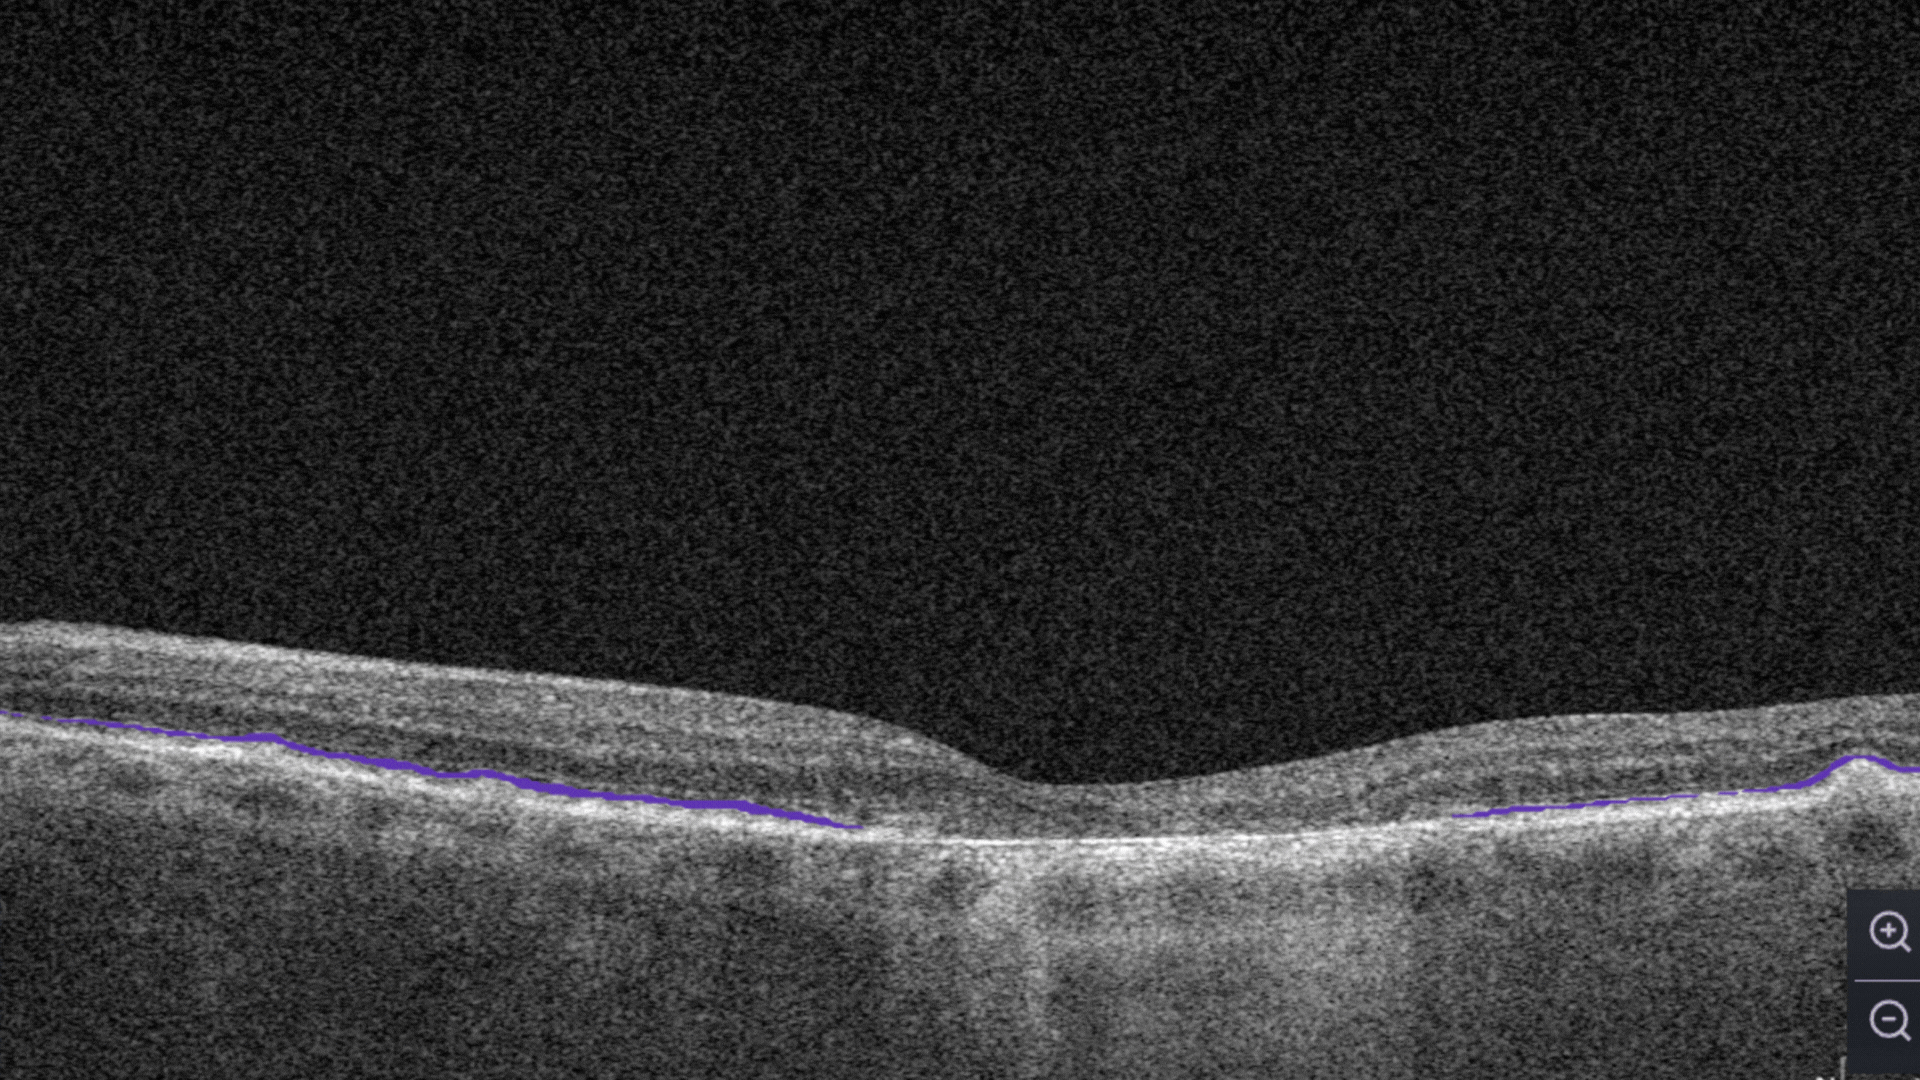

Ellipsoid zone disruption. Changes in the photoreceptor layer can be identified as a disruption or defect in the ellipsoid zone (EZ).

RPE disruption. Elevation of the Retinal Pigment Epithelium layer.

Ellipsoid zone disruption is the changes in the photoreceptor layer can be identified as a disruption or defect in the ellipsoid zone (EZ).

RPE Disruption is the disruption of the Retinal Pigment Epithelium layer